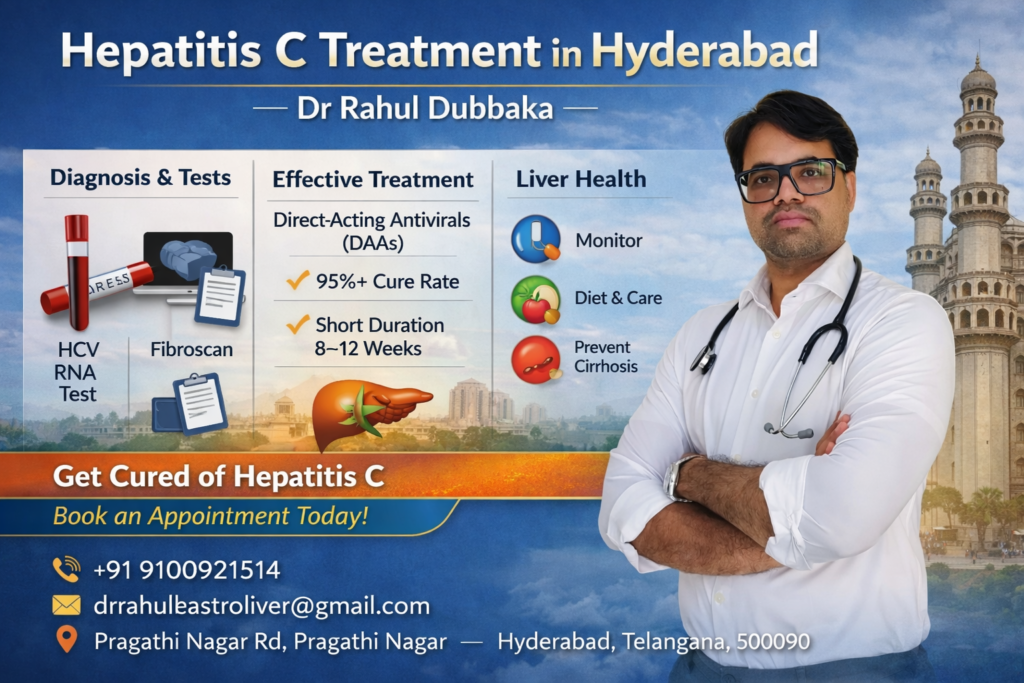

Hepatitis C Treatment in Hyderabad – Expert Care

Looking for Hepatitis C treatment in Hyderabad? Dr Rahul Dubbaka offers advanced antiviral therapy with 95%+ cure rates at People’s Hospital, Pragathi Nagar. Book your consultation today at +91 9100921514. Hepatitis C is a viral infection that primarily affects the liver and can silently damage it over time. If left untreated, it may lead to serious complications such as cirrhosis, liver failure, and even liver cancer. The good news is that with modern medical advancements, Hepatitis C is now highly curable with effective antiviral medications.

If you are searching for Hepatitis C Treatment in Hyderabad, consulting an experienced gastroenterologist and hepatologist like Dr Rahul Dubbaka can ensure accurate diagnosis, personalized treatment, and long-term liver health management.

Dr Rahul Dubbaka practices at People’s Hospital, offering advanced liver care services for patients across Hyderabad.

Why Choose Dr Rahul Dubbaka for Hepatitis C Treatment in Hyderabad?

Dr Rahul Dubbaka is a reputed gastroenterologist and liver specialist with expertise in managing chronic liver diseases.

Key Advantages:

Specialized expertise in liver disorders

Advanced diagnostic facilities

Personalized antiviral treatment plans

Regular monitoring and follow-up

Patient-focused approach

At People’s Hospital, patients receive comprehensive care in a well-equipped medical environment.

Diagnosis of Hepatitis C

Accurate diagnosis is essential before starting treatment.

1. HCV Antibody Test

Detects exposure to the virus.

2. HCV RNA PCR Test

Confirms active infection and measures viral load.

3. Liver Function Tests (LFTs)

Assess liver inflammation and damage.

4. Fibroscan / Ultrasound

Evaluates liver fibrosis or cirrhosis.

5. Genotype Testing

Helps determine the most suitable antiviral regimen.

Modern Treatment Options for Hepatitis C

The introduction of Direct-Acting Antivirals (DAAs) has revolutionized Hepatitis C treatment.

Benefits of DAA Therapy:

8–12 weeks oral medication

Over 95% cure rate

Minimal side effects

No injections required

Safe for most patients

Book Your Hepatitis C Consultation Today

If you or a loved one has been diagnosed with Hepatitis C, consult Dr Rahul Dubbaka at People’s Hospital for expert evaluation and advanced treatment.

📍 People’s Hospital

Plot No. 755A, 1st Floor, Pragathi Nagar Rd,

Near Three Monkeys Statue, Pragathi Nagar,

Hyderabad, Telangana 500090

📞 +91 9100921514

📧 drrahulgastroliver@gmail.com